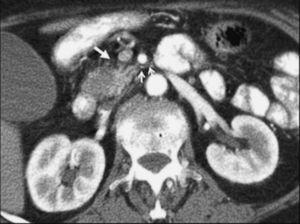

La TC helicoidal permitió, además, llevar a cabo un estudio detallado de los pequeños vasos arteriales y venosos peripancreáticos24-26 (fig. 2), mostrando mejores resultados que la angiografía por sustracción digital en el diagnóstico de la invasión vascular por cáncer de páncreas27. La valoración de estas pequeñas estructuras vasculares mejora el rendimiento de la TC en la estadificación tumoral28,29. La posibilidad de reconstruir en diferentes planos del espacio las imágenes axiales obtenidas ha sido evaluada por algunos autores30,31, obteniendo un mayor rendimiento de la TC para determinar la invasión vascular, fundamentalmente venosa, cuando las secciones transversas se interpretan en combinación con las reconstrucciones multiplanares que cuando se interpretan únicamente las secciones transversas (92-96% frente a 69-70%) (fig. 3).

Fig. 2.--Estudio de tomografía computarizada con contraste endovenoso en fase pancreatográfica en un paciente con neoplasia del cuerpo pancreático. Múltiples vasos mesentéricos dilatados secundarios a la infiltración venosa portomesentérica tumoral (flechas).